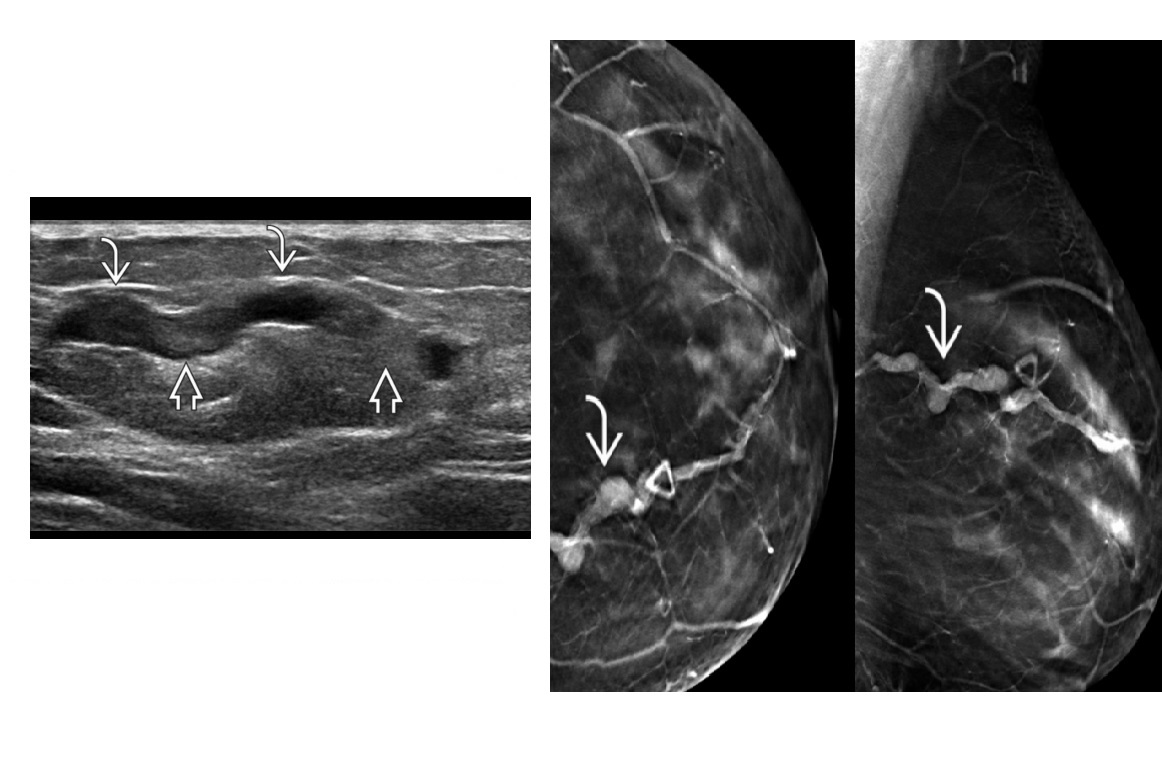

Intracapsular vs extracapsulat implant rupture. what signs?

A

Intracapsular

- Linguine on MRI

- Stepplader on US

Extracapsular

- Snowstrom on US

Water-suppressed STIR: Only silicone is bright

Depict extracapsular silicone, extent